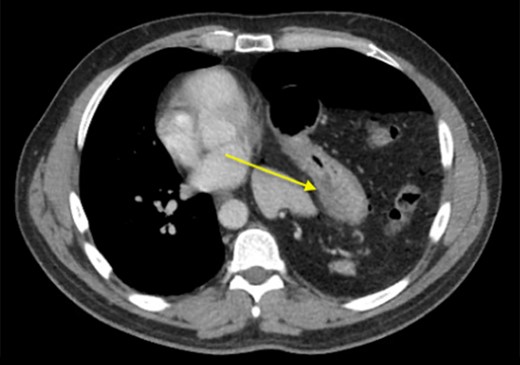

Two days later, the patient re-presented to the emergency department with left-sided pleuritic chest pain. The heart rate was 92 beats/min and the respiratory rate was 23 breaths/min on room air. The patient was stable, looked well, and his pain resolved almost entirely at time of examination. Clinically relevant labs showed a WBC of 8 × 109/L (normal range: 4–11 × 109/L). The CT did not show any significant enlargement of pneumoperitoneum; however, significant rightward shift of the mediastinum was noted. So we suggested worsening tension in the left hemithorax with further collapse of the left lung (Fig. 3). Despite being clinically stable, the mediastinal shift which was not present on the previous admission was concerning and thus the patient was taken to the operating room with the decision to repair the hernia. A left thoracotomy was used to enter the chest cavity. There was severe atelectasis of upper and lower lobes. We immediately noted a large hernia sac which encompassed the entire chest cavity and the remaining diaphragmatic muscle was significantly thinned out. The hernia sac was opened in order to identify the source of the pneumoperitoneum seen on imaging which we had suspected to be of gastric origin. Upon examination of the abdominal contents which required meticulous dissection off the herniated diaphragm from chronic adhesions, we were able to identify a well-developed perforated gastric ulcer on the anterior surface of the greater curvature of the stomach (Fig. 4). This ulcer was resected with a wedge GIA stapler and the hernia was subsequently closed by bringing the muscles together and imbricating the closure with the redundant sac using prolene sutures. Upon closure, we did not place a mesh due to the possible contamination from the gastric perforation. When the repair was complete and the patient taken off the one-lung ventilation, his lungs immediately pinked up and re-expanded. Overall, the patient tolerated the procedure very well without any post-operative complication. Two days later, we carried out an upper GI series which showed no evidence of any extravasation and his diet was advanced. On the sixth post-operative day, the patient was discharged home. He was re-evaluated in clinic 2 weeks later and continued to progress well with a stable repeat chest x-ray (Fig. 5).